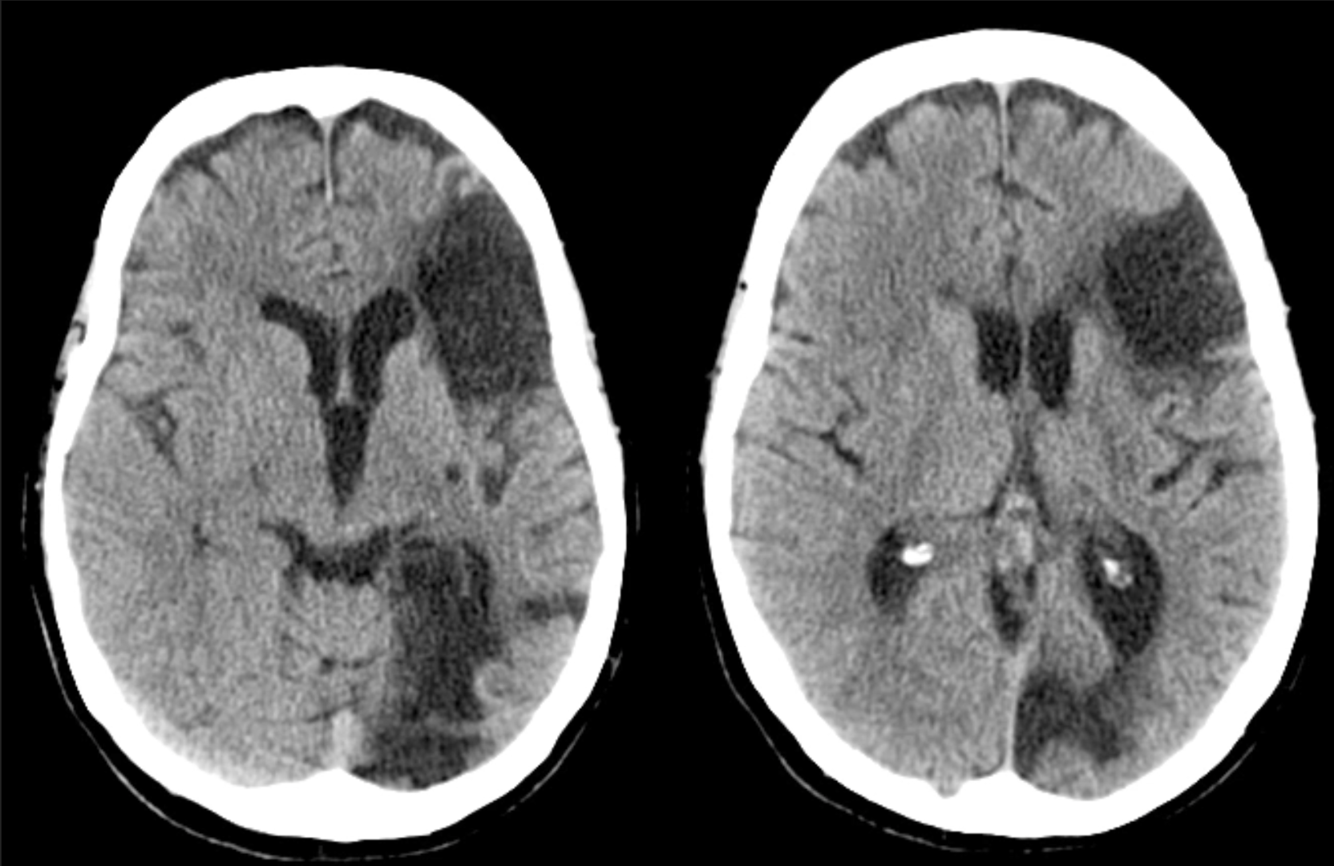

39 y/o M found down.

Intraventricular bleed due to AVM